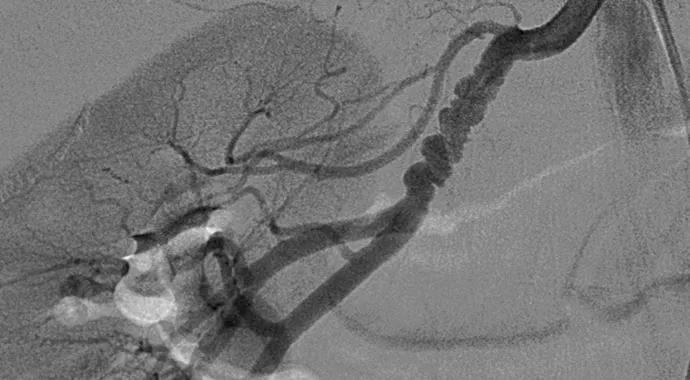

Angiogram images of FMD

FMD is a nonatherosclerotic arterial disease of medium-sized vessels, most commonly the renal and extracranial carotid and vertebral arteries, that leads to arterial stenosis, occlusion, dissection and aneurysm. Although its causes and prevalence are not well understood, it is recognized that more than 90 percent of patients are women, often in their 40s or 50s.